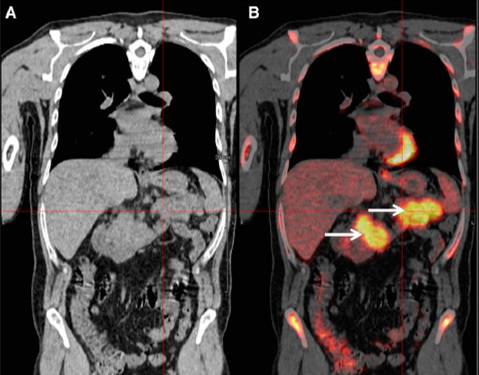

天津市肿瘤医院血液科与放射科合作,开展了全身低剂量CT在多发性骨髓瘤中应用的临床试验,欢迎广大患者积极入组。MRI和PET/CT的敏感性和特异性均较高,且功能性成像可以反映肿瘤负荷与肿瘤细胞的代谢活性,是更为准确的检测手段,研究表明MRI和PET/CT上的变化均与实验室检查有一定关联,并可用于疗效评价等。MRI对软组织和骨髓的分辨率很高,是检测弥漫性骨髓浸润和压缩性骨折的最敏感的手段,MRI还可以区分骨质疏松的良恶性,以此来评估骨折风险,但MRI检查时间长,不能用于有幽闭恐惧症、金属物和假体的患者,对于整个骨骼系统的视野较局限。18F-FDG PET/CT虽然对脊柱的敏感性不如MRI,但具有可以在出现溶骨性病变之前就反映出新陈代谢的变化,能够直观地显示出肿瘤负担的优势。

图4.PET/CT下的MM病灶